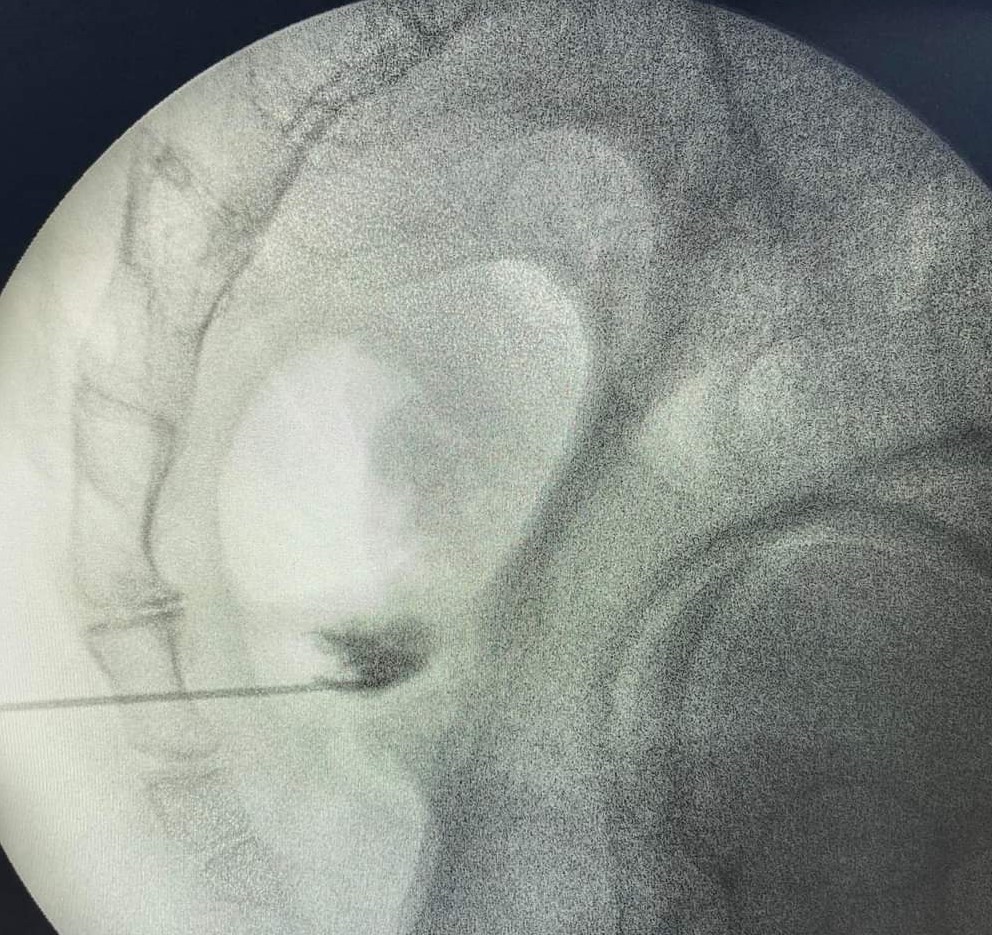

Πρόκειται για δυο τεχνικές που στοχεύουν στη διακοπή της μετάδοσης των σημάτων πόνου κατά μήκος των νευρικών οδών. Η πρώτη μέθοδος χρησιμοποιεί ραδιοσυχνότητες για να το πετύχει αυτό και η δεύτερη υγρό άζωτο που είναι ψυκτικός παράγοντας. Εφαρμόζονται σε ξύπνιο ασθενή με τοπική αναισθησία και κάτω από ακτινοσκοπική καθοδήγηση. Προσφέρουν σημαντική ανακούφιση για μήνες και επαναλαμβάνονται ως πράξεις εάν χρειασθεί μετά το πέρας της διάρκειας δράσης.

Ο κίνδυνος επιπλοκών είναι χαμηλός. Στις επιπλοκές ανήκουν η λοίμωξη, η ανάπτυξη αιματώματος, η βλάβη νευρικών και γύρω δομών. Η κινητική βλάβη του νεύρου αποφεύγεται με τη χρήση παλμικής ραδιοσυχνότητας ή κρυοπηξίας.